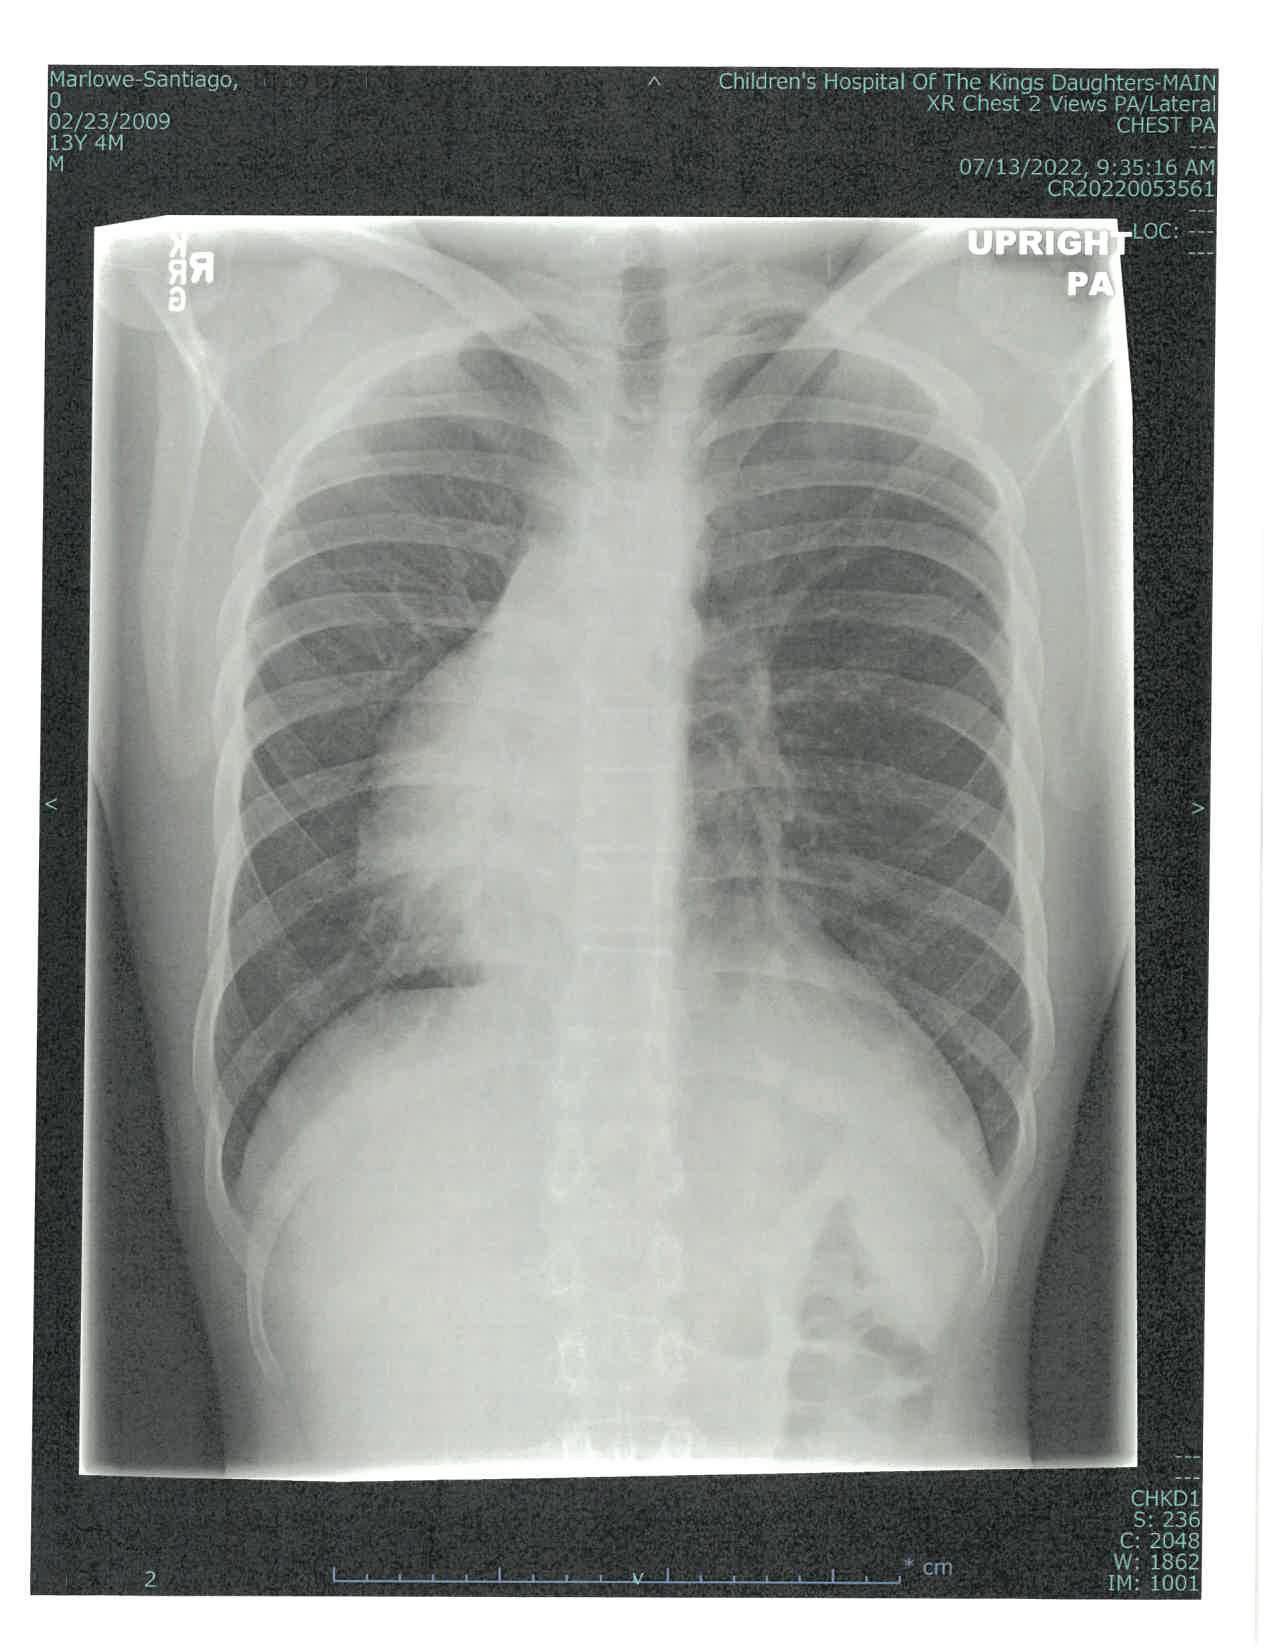

Thomas Marlowe-Santiago finds new confidence after chest wall reconstruction and years of specialty treatment at CHKD

Thomas Marlowe-Santiago has been coming to CHKD since the day he was born, when doctors in the delivery room noticed something odd about his heartbeat: it was loudest on the right (or in this case, wrong) side of his chest.

Thomas has a condition called situs inversus, which means his internal organs are on the opposite side of the body from those with normal anatomy. This mirror-image flip is one aspect of a genetic condition that Thomas has called Kartagener syndrome, which also involves dysfunction of cilia, tiny hair-like structures that are essential for a wide range of functions in the body. In Thomas’ case, this dysfunction causes him to experience frequent respiratory and sinus infections.

Since his first transfer to CHKD’s Neonatal Intensive Care Unit, Thomas has been hospitalized at CHKD several additional times for pneumonia and bronchitis. Over his 16 years, the Virginia Beach teen has been treated by a host of specialists at CHKD, including pulmonologists; cardiologists; ear, nose, and throat surgeons; and allergy, asthma, and immunology specialists. He does physical therapy every day, wearing a special vest that vibrates to help dislodge mucus and keep his lungs clear. He also takes medications for asthma and allergies.

But that’s not all this brave young man has had to deal with. He also has Poland syndrome, which is characterized by a missing pectoralis muscle, in his case on his left side. And, as a teen, Thomas developed pectus excavatum, a condition in which the chest wall sinks in toward the spine.

Fortune was on Thomas’ side in another respect, however. His hometown, go-to hospital that has treated him since birth just happens to be the top international center for the treatment of pectus excavatum.

Thomas’ case definitely fell into the “most complex” category, says CHKD surgeon Dr. Franklin Margaron, who treated Thomas. “Thomas’ muscular asymmetry and underlying respiratory issues presented challenges,” says Dr. Margaron. “When you and I inhale, our sternum expands outward,” he explains. “Thomas’ sternum rotated inwards toward his heart and lungs when he inhaled.

“Severe pectus excavatum like Thomas’ can cause direct cardiac compression, which can lead to valvular dysfunction, arrhythmias, and a number of different problems,” says Dr. Margaron. “For Thomas, that would have potentially led to shortness of breath and

inability to engage in activities he would otherwise be able to do.”

In addition, the chest can be very sensitive for weeks after the Nuss procedure. Surgeons use curved metal bars that go under the sternum and are affixed to ribs to press the sternum and ribs out into a normal shape. The bars remain in place for several years while the chest wall matures and hardens.

Dr. Margaron was concerned that the agitation from Thomas’ compression vest might be very painful, or even dislodge the Nuss bars from their proper position. But if Thomas doesn’t use his vest every day, he risks developing lung infections, including pneumonia.

“Thomas’ unique physiology called for a dramatic degree of correction combined with the most stability we could offer,” says Dr. Margaron.

For Thomas, Dr. Margaron opted to use a system of surgical instruments and implants developed in Korea by Dr. Hyung Joo Park. The Park system is a variation of the Nuss procedure that uses additional bars and a different system of anchoring them to offer additional stability.

Thomas went into surgery on December 20, 2022. “This was the first major surgery that my son ever had. I was petrified that something would go wrong,” says Lisa

Since having metal bars placed into his chest to reshape his sternum, Thomas says he can finally take a deep breath. After three years of follow-up checkups and imaging, he expects to have the bars removed in early 2026.